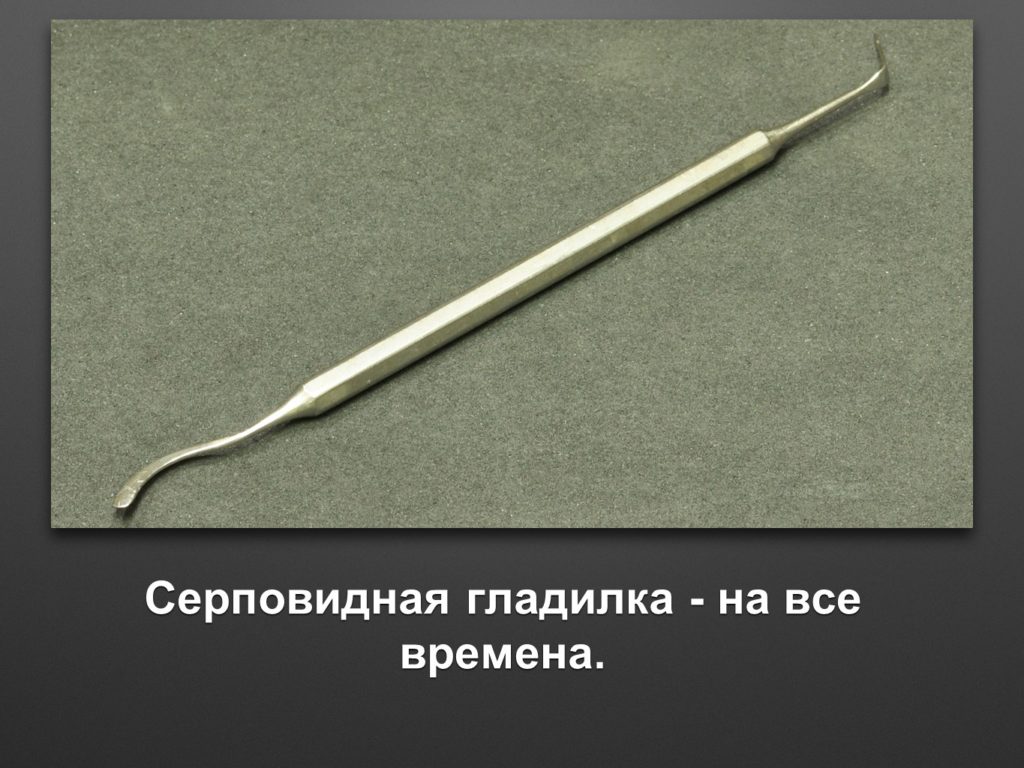

"Выстраданные" наборы инструментов

Все ниже перечисленные инструменты можно приобрести на сайте kohlermed.ru или связаться с нашим менеджером по тел 499-5179401

Все ниже перечисленные инструменты можно приобрести на сайте kohlermed.ru или связаться с нашим менеджером по тел 499-5179401